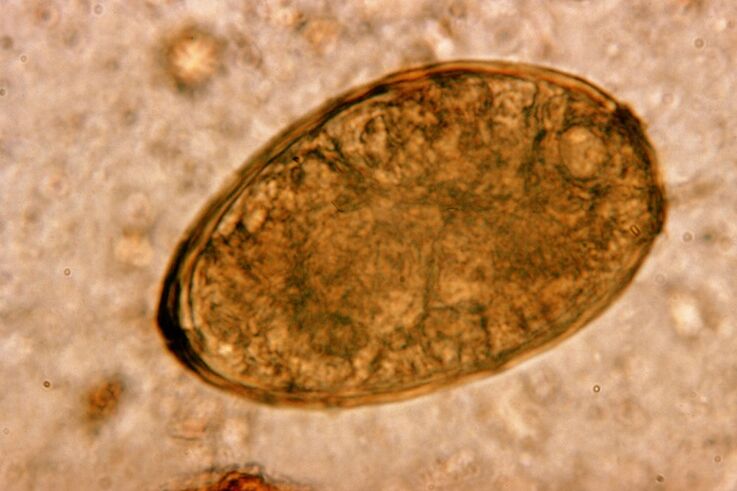

A trematoda vive en pares nos pulmóns e forma quistes nos bronquios. A infestación prodúcese cando se consumen cangrexos e lagostinos infectados co parasito. No tracto gastrointestinal, o fluke pulmonar penetra no peritoneo e entra nos pulmóns a través do diafragma, o que fai que o paciente tose de forma persistente.

O pequeno verme do pulmón, que pertence á clase dos trematodos, está "especializado" en parasitar especificamente nos pulmóns. Provoca problemas no sistema respiratorio moito máis graves que, por exemplo, as vermes redondas.

Os infiltrados e hemorraxias ocorren no lugar de localización, creando cavidades cheas de metabolitos podrecidos de vermes, parasitos mortos e tecido pulmonar. O dano causado pola trematoda pulmonar vén agravado polo feito de que é un fígado longo que pode vivir no corpo do hóspede ata 20 anos.